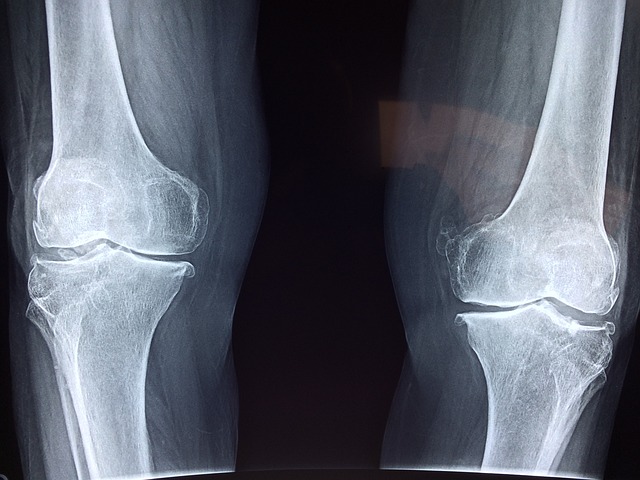

한쪽무릎이 아파지면 자연히 다른쪽도 함께 무리가 가기마련인데요.

한쪽 무릎을 기준으로 대게 250~500만원선으로 책정이 되어있습니다.